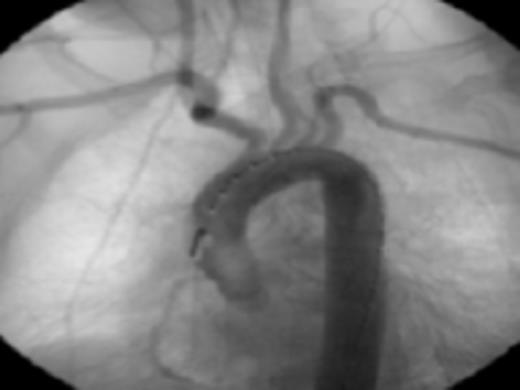

Fig 4: Post endovascular stenting angiography showing appropriate seal without leaks or extravasation of contrast

Her past medical history of considerable GI bleeds and her significant fall risk made her a poor candidate for continued anti-coagulation therapy. The appropriateness of the lesion involved and her risk for further embolic events guided selection of endovascular technique for treatment. Exclusion was performed by a 26mm × 10cm thoracic aortic stent graft with balloon angioplasty. Post-procedure angiography confirmed position of the graft distal to the origins of the great vessels and did not demonstrate any leaks. Subsequently, she progressed well and was discharged in stable condition on warfarin and clopidogrel.